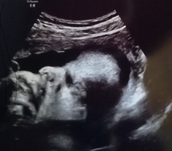

die Nacht war furchtbar ich hab kaum geschlafen. Haben uns entschieden nicht ins KKH gestern Abend zu fahren, da kein Blut mehr kam. Heute morgen eher bräunliches Blut.. bin direkt zum FA. Sie meinte besser könnte es auf dem Ultraschall gar nicht aussehen. Das Herzchen hab ich zum 1. mal kräftig schlagen sehen. Sie meinte wir müssen jetzt abwarten aber eig schaut alles gut aus. Ich brauch jetzt viel Ruhe, kein Stress... sie hat mich ab heute und die komplette nächste Woche krank geschrieben. Büro-Stress ist auch schon zu viel meinte sie. Soll mich entspannen und auf eine Art Wellness machen.. muss jetzt famentina nehmen.. mir ist so ein Stein vom Herzen gefallen. Allerdings bin ich trotzdem besorgt.. das ist grade ein hoch und ab der Gefühle. Aber erstmal danke ich dem lieben Gott dass alles gut ist ♥️ Danke euch allen für die lieben Worte und das ihr an uns gedacht habt 😘 liebe Grüße MRs-Balu & Krümel ♥️